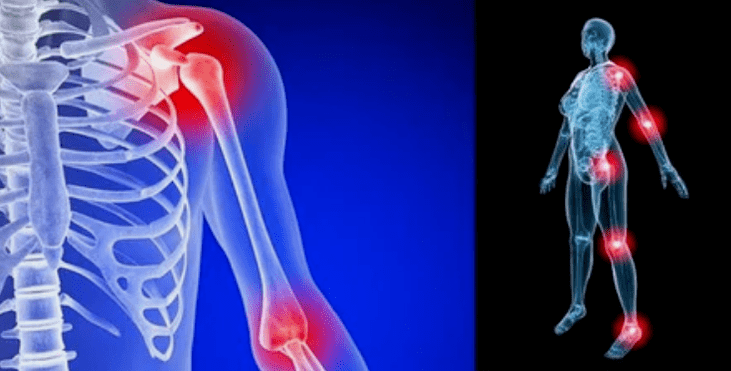

As manifestacións da enfermidade difiren pouco dependendo da localización, a miúdo os signos reflíctense nos xeonllos, nas xuntas de ombreiro e na cadeira debido á alta carga.

As causas da artrose das articulacións difiren segundo a forma de patoloxía. A artrose deformante da articulación do cóbado, a articulación do nocello e a artrose do ombreiro ás veces desenvólvense sen causas notables, é posible detectalas cun médico, un especialista en reumatoloxía. Se o problema non estaba precedido de patoloxías visibles, a enfermidade chámase primaria. A forma secundaria de violación é diagnosticada principalmente, pode provocar varios estados.